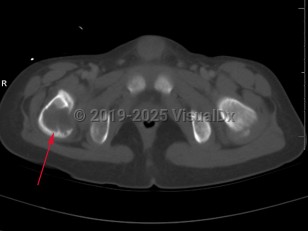

The clinical presentation of EG depends largely on the location affected. EG is most often confined to the axial skeleton. EGs are often asymptomatic and found incidentally, or may initially present with pain and swelling of the affected area, with or without decreased range of motion. Commonly affected areas of the skeleton include (in order of frequency): skull, femur, pelvis, mandible, clavicle, ribs, and long bones (of the diaphysis and metaphysis).